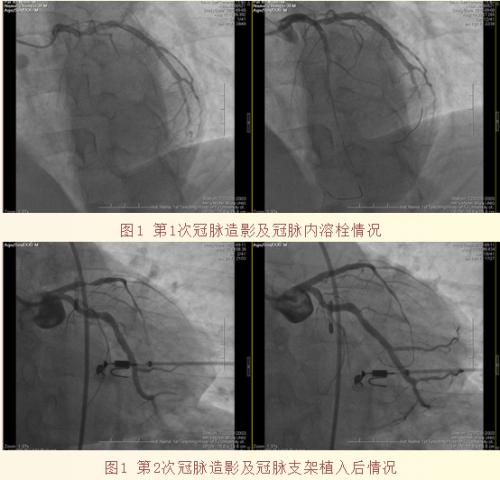

患者,男性,38岁,因血糖控制不佳就诊于华人策略内分泌科,住院期间TNT、心肌酶显著升高,考虑“急性心肌梗死”,立即转入心血管科重症监护室(CCU),急查冠脉造影显示:前降支起始100%闭塞,病变血管属于极其重要的主干血管,血栓负荷重,病情危急,如何在极短时间内做出最佳治疗策略的选择?如果此时贸然植入支架,易损伤远端微循环,产生慢血流/无复流现象,会导致患者本就十分脆弱的心功能进一步恶化。此外,患者虽然患有糖尿病,但年仅三十八岁,如果仅因急性血栓引起心肌梗死,植入支架就更应该慎重。患者年纪轻轻、家属殷殷期盼,不能让突来的疾病摧毁一个幸福的家庭。综合考虑后,选择在IABP支持下行冠脉内溶栓,冠脉血流恢复后,安返病房,予以强化抗栓治疗,待病情稳定、心功能改善后,再次进行冠脉造影显示冠脉血栓完全溶解,冠脉血管存在狭窄,于前降支病变处成功植入1枚支架,术后复查心脏超声提示室壁瘤消失,心功能恢复正常。

该例病人为前降支近段100%闭塞,前降支是冠状动脉血管中功能最强大的血管,近段闭塞等同于左主干病变,其危重性不言而喻,根据病变的具体情况,选择适宜的手术策略则是该例患者抢救成功的关键!(心血管科供稿 通讯员 刘宇)